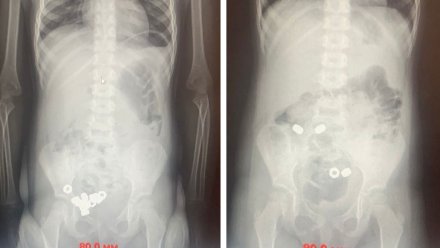

Трёхлетний малыш проглотил 16 гаек в Воронеже. Его доставили в детскую клиническую больницу №2, сообщили в пресс-службе регионального минздрава в понедельник, 17 ноября.

Врачи осмотрели пациента, однако у него не было никаких симптомов проглатывания инородных тел. Медики сделали малышу рентген – там и нашли 16 гаек.

Сотрудники больницы оставили ребёнка под наблюдением. Пациенту назначали диету, покой, рентген и контроль стула. Все инородные тела вышли естественным путём. Малыша выписали.